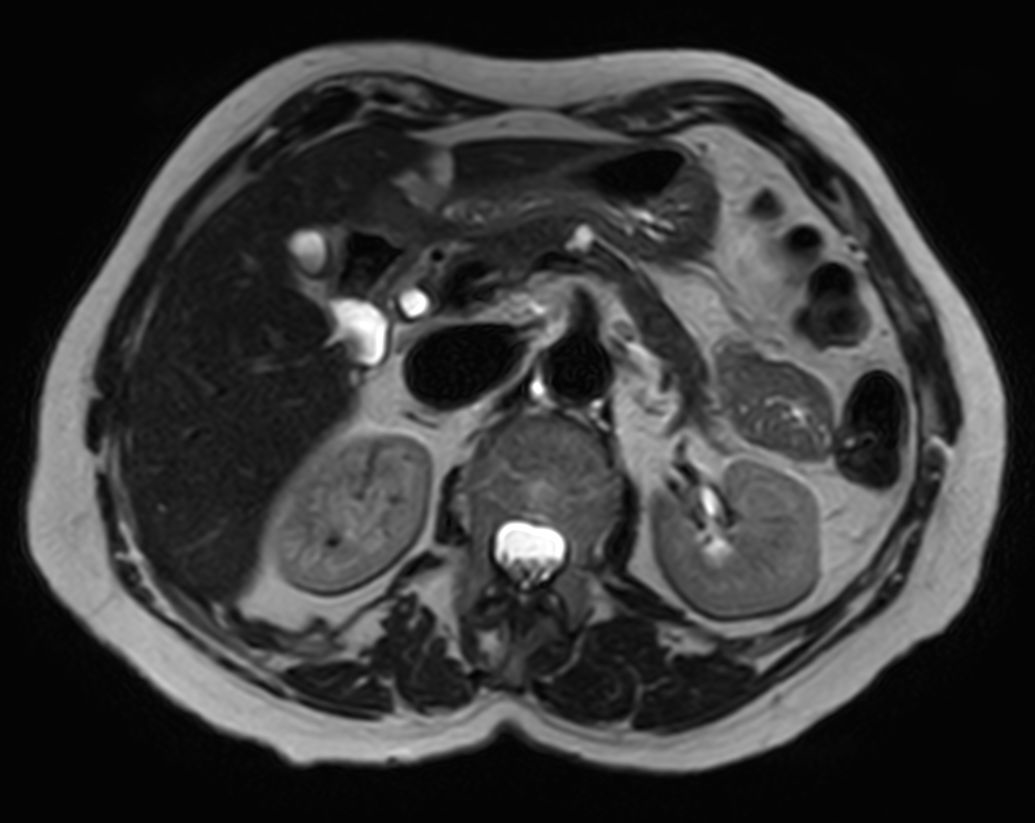

Pancreas nodule – Free breathing

Patient with a pancreas nodule. ExamCard includes Compressed SENSE to shorten the breath hold time, VitalEye for touchless respiratory sensing, MultiVane XD to acquire motion-free diagnostic images and 4D FreeBreathing to perform multi-phase contrast-enhanced Liver MRI studies.

T2w TSE - Breath hold Compressed SENSE